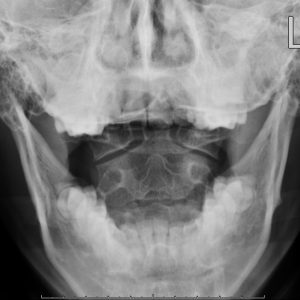

C1 & C2 ( Open Mouth )